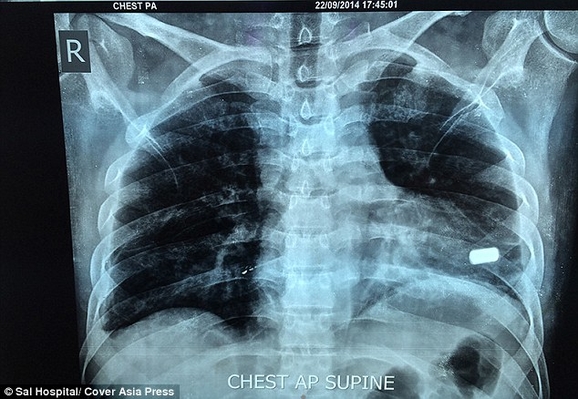

32-летний индиец Бхарат Шарма из города Алигарх, что в штате Уттар-Прадеш, Северная Индия, два месяца прожил с пулей в сердце. 22 июля мужчина стал случайным свидетелем ограбления банка, за что и пострадал. Один из грабителей открыл огонь, в результате чего в Бхарата попало две пули. Одна из них угодила в левый бок индийца и не задела жизненно важных органов, другая же попала прямо в сердце.

Из тела чудом выжившего мужчины одну пулю извлекли только через неделю после нападения, а другую, опасаясь за его жизнь, удалять отказались.

Доктор Анил Джейн, кардиохирург, который руководил операцией, сказал, что это был очень редкий случай, и удивительно, что пациент жил с пулей в сердце в течение двух месяцев: "Пуля находилась в сердечной мышце у верхушки левого желудочка, одной из двух камер сердца. Это уникальный случай, который запросто мог стать фатальным. То, что он прожил два месяца с пулей в таком месте - уникальный случай, это очень счастливый человек"

Во время трехчасовой операции команде из пяти врачей пришлось остановить сердце пациента и поддерживать его с помощью аппарата искусственного кровообращения. Только так они могли извлечь пулю. Оперативное вмешательство прошло успешно и сейчас Бхарат Шарма восстанавливается в отделении интенсивной терапии больницы. Пулю, которая в любой момент могла его убить, он хочет сохранить в качестве напоминания о том, как близко он подошел к смерти.